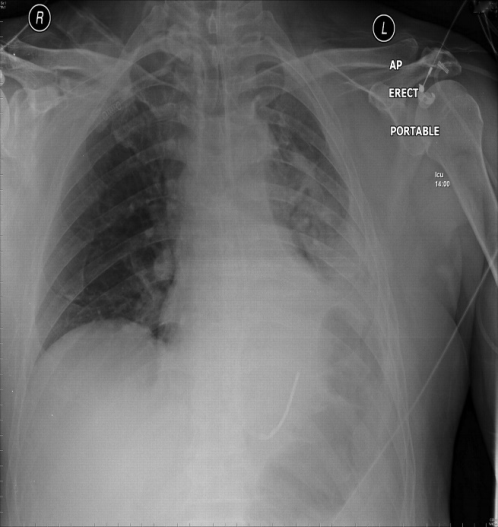

Fig. 4: Chest X-ray showing ventilator-associated pneumonia